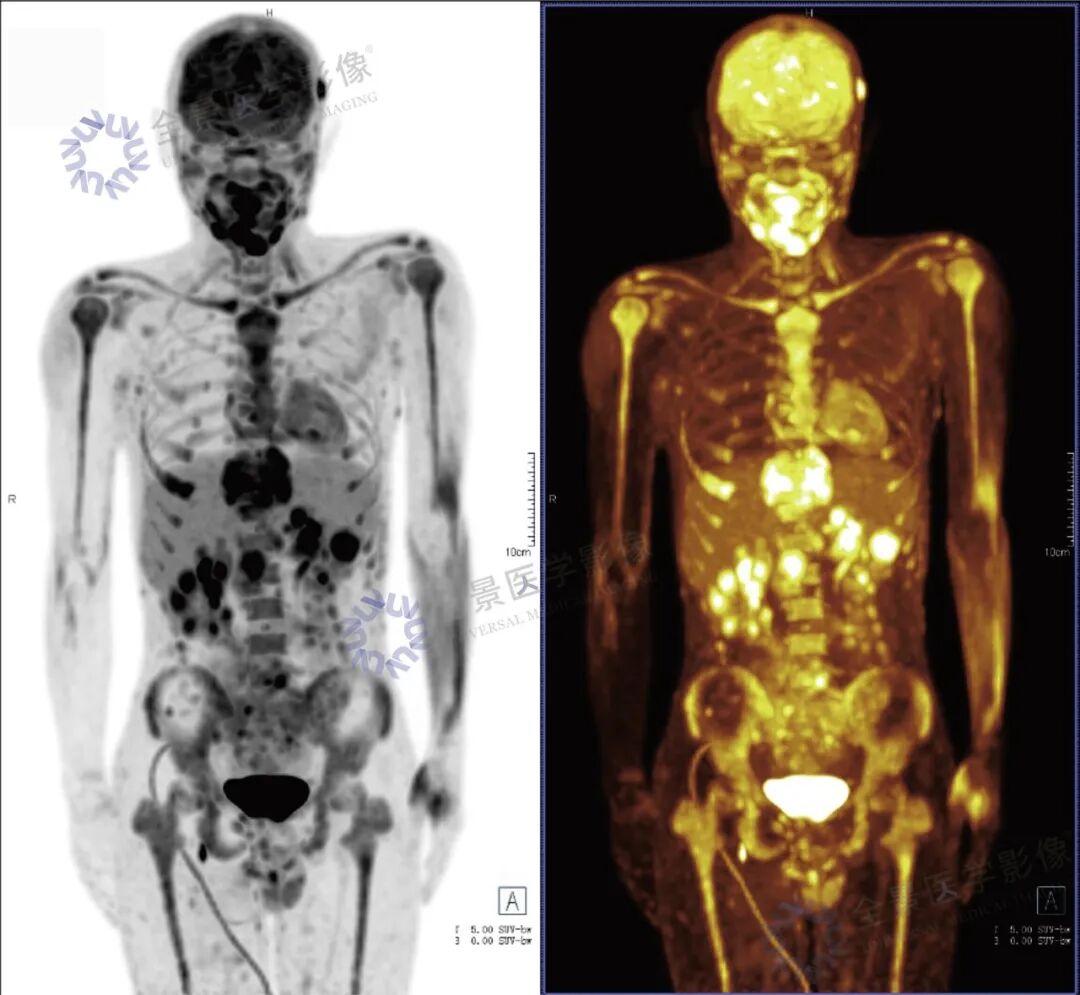

张先生(化名),因持续3个多月的腹痛、腰痛在外院就诊。初始CT检查发现其胸11椎体骨质破坏伴周围软组织肿胀,考虑为“脊柱结核”等感染性病变,并接受了中药治疗。然而,两个月后,张先生又出现了新的症状——牙痛。 经病理活检及免疫组化检查,最终确诊为极为罕见的Erdheim-Chester病。为全面评估这一可累及全身多系统疾病的侵犯范围、明确病灶活动性,并为制定精准治疗方案提供依据,张先生进行了全身PET/CT检查。 PET/CT检查图像: PET/CT检查结果: (1)中轴骨及四肢骨广泛FDG代谢活跃伴信号异常;其中胸10、胸11椎体病灶周围软组织增厚,累及邻近椎管内及双侧椎间孔、双侧胸膜,并与主动脉分界不清。 (2)全身皮下及肌层内多发结节及肿块,FDG代谢活跃;全身软组织广泛肿胀。 (3)鼻咽各壁增厚,顶后壁为著,FDG代谢活跃。 (4)甲状腺多发结节,FDG代谢活跃;双肾及胰腺多发结节及肿块,FDG代谢活跃;双侧阴囊内异常信号伴FDG代谢活跃; (5)左侧锁骨上窝、纵隔内(2L区、3A区)、降主动脉旁、左侧横膈前组、右侧腋窝、左肾周间隙、肠系膜区、双侧髂血管旁多发淋巴结,FDG代谢活跃; (6)心包局部呈结节状稍增厚,FDG代谢轻度活跃; 综上,结合临床,均考虑Erdheim-Chester病所致。 此次PET/CT不仅证实了已知的脊柱病变,更一次性揭示了临床尚未怀疑的、广泛存在于内脏、淋巴结及软组织的隐匿病灶,为疾病分期与治疗提供了决定性依据。